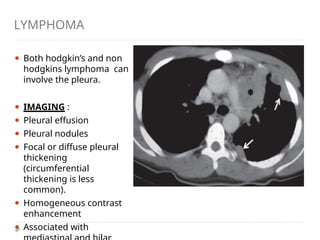

LYMPHOMA

⚫ Both hodgkin’s and non

hodgkins lymphoma can

involve the pleura.

⚫ IMAGING :

⚫ Pleural effusion

⚫ Pleural nodules

⚫ Focal or diffuse pleural

thickening

(circumferential

thickening is less

common).

⚫ Homogeneous contrast

enhancement

⚫ Associated with

Pleural lymphoma: Axial contrast-enhanced CT scan

showing heterogeneously enhancing lobulated mass

lesion involving the diaphragmatic pleura (arrow) and

invading the chest wall in a case of high-grade

PLEURAL METASTASES